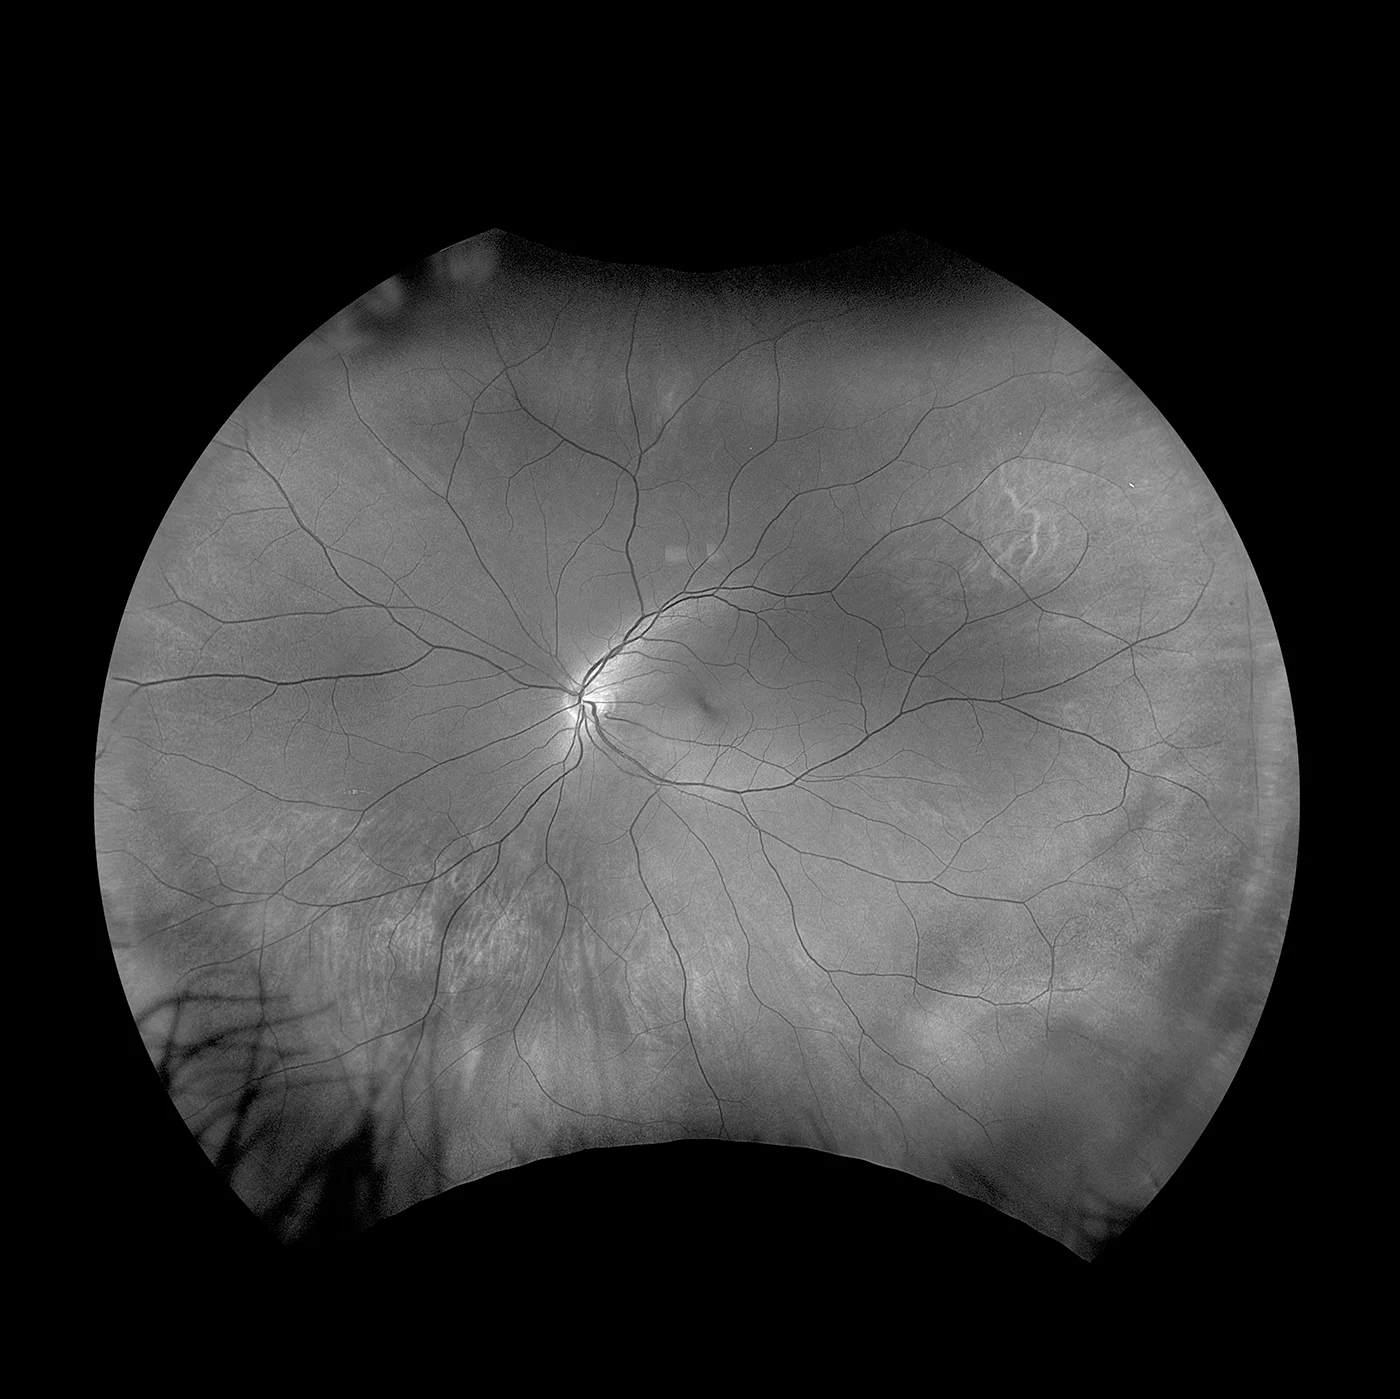

- Fluoreszenzangiographie

- Indocyaningrün-Angiographie